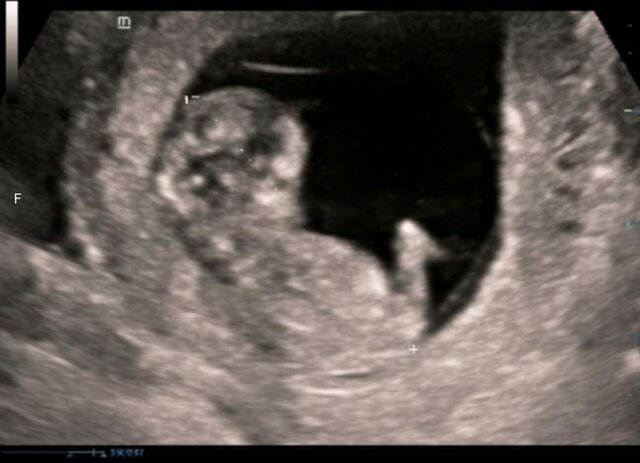

• Mi primer hijo

Mi primer hijo

En este eventos se usaron dos inteligencias, la inteligencia intrapersonal y la inteligencia naturalista, la primera me llevo a cuestionarme sobre mi, que pienso, que siento, que quiero y como voy a saber hacer este nuevo rol en mi vida y la segunda ya que el proceso que vivo como mujer al darle vida a un ser humano es una experiencia jamás vivida, pero sobre todo como el ámbito natural implica y es participe para que todo salga bien.